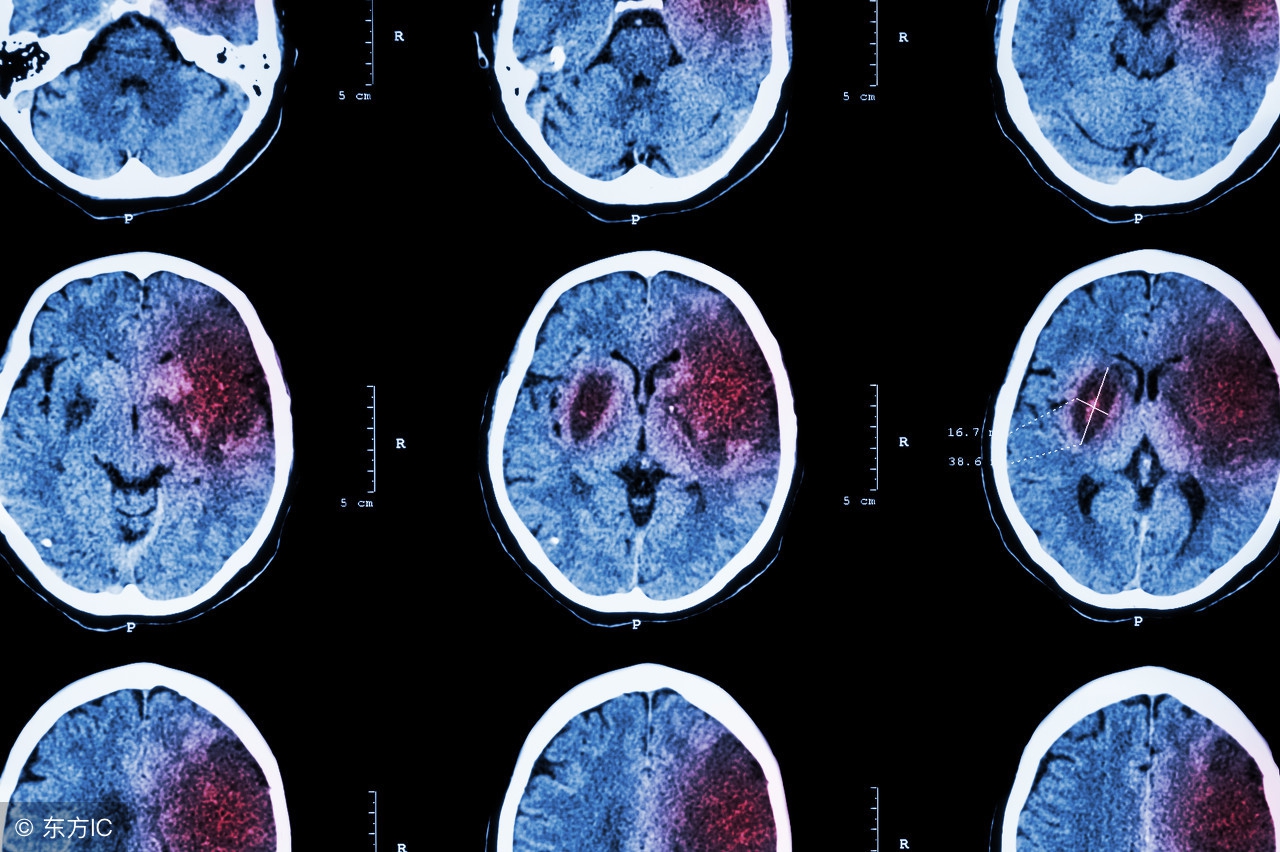

脑中风又称脑卒中或脑血管意外,是指人体脑部血管由于某种原因而造成颅内血液供应障碍,引起脑组织损害的一组疾病。具有极高的病死率和致残率,主要分为出血性脑中风(脑出血或蛛网膜下腔出血)和缺血性脑中风(脑梗塞、脑血栓形成)两大类,以脑梗塞最为常见。脑中风发病急,病死率高,是世界上最重要的致死性疾病之一。

11、脑中风应送医院进行CT检查,区分脑中风的类型,针对病因进一步治疗。搬运病人时尽量保持平稳。